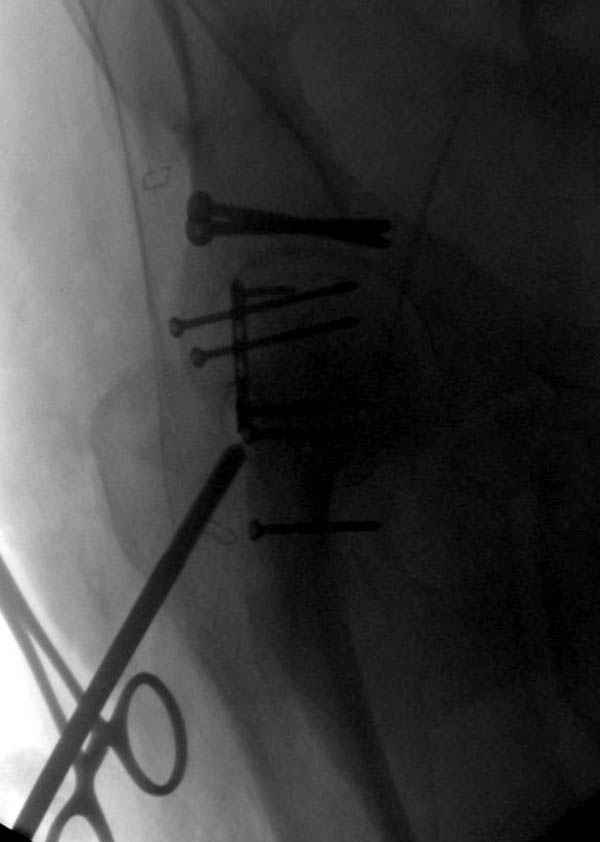

На седьмой день зафиксирован перелом ацетабулума через задний доступ. Перед операцией для профилактики DVT, IVC фильтер, также получает Lovenox.

Латеральное положение облегчает проведение тракции через вертел, за 5 мм стержень за вертел (грузом через тракционное приспособление), на обычном рентгенопрозрачном операционном столе, а для положения на животе, наверное, Judet Table более приемлем, потому что там имеется латеральное тракционное устроиство.

Там множество обычных 2.7 мм шурупов, потом идет фиксация основными пластинами.

Снимки здесь....